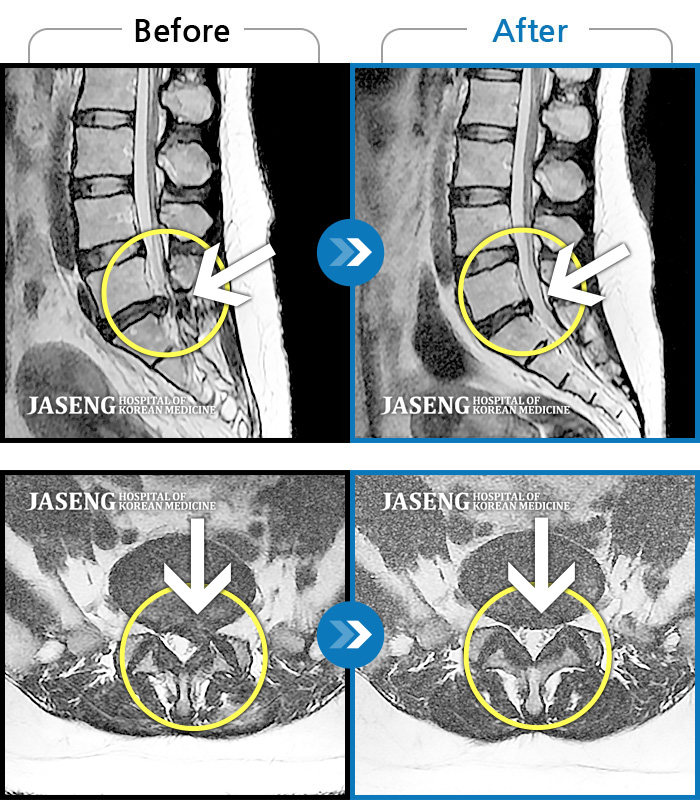

허리디스크

일산 · 김태용 원장

허리와 좌측 다리가 당겨 보행이 불가능했다.

촬영시기

2020.02.10 ~ 2021.02.22

2021.02.26